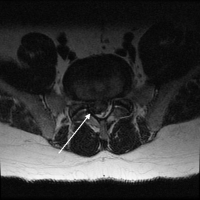

The treatment of cauda equina syndrome is a quick diagnosis normally by MRI scan and surgical decompression of the nerves. Normally, this surgery is a microdiscectomy. You can see an example of an actual cauda equina syndrome and decompression surgery by watching the video attached to this section.